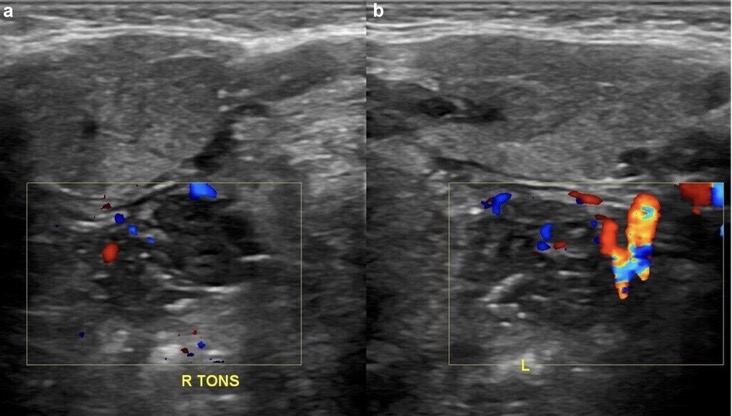

4. Augmentation de la vascularisation amygdalienne interne

(D) Vascularisation intra-nodale accrue et irrégulière